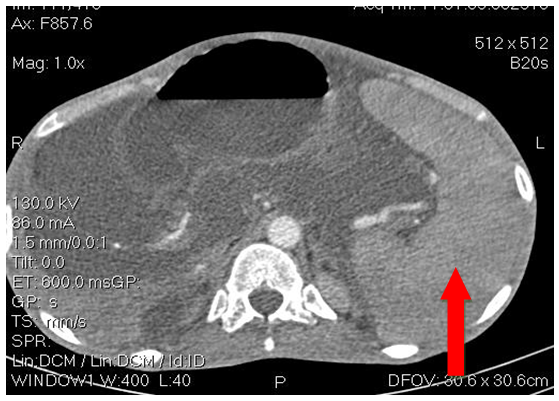

He was a 23-year-old male with no previous history, including no ethylo-smoking or cardiovascular pathology, admitted in November 2018 for diffuse, atrocious, diffuse abdominal pain, sudden twisting associated with vomiting and a cessation of materials and gases. The physical examination revealed an abdominal meteorism. The unprepared abdomen radiograph (ASP) had objectified hydro-aerobic levels wider than high. Acute intestinal obstruction by volvulus of the hail was suspected. He underwent an emergency laparotomy which revealed acute mesenteric ischemia for which an ileal resection of approximately 1.5m with terminal ileo-ileal anastomosis was performed. The postoperative effects were marked by the recurrence of the mesenteric infarction clinical presentation one week later requiring surgical resection with a new 50cm ileum resection and terminal ileo-ileal anastomosis. The evolution was marked by the appearance of an alteration of the general state (performance status index at 2 according to the World Health Organization); with anorexia, significant weight loss, malabsorption diarrhea made of liquid stools, at least 10/day containing food residues; with the occurrence of ascites whose puncture shows a liquid low in protein at 0.59g/l. The patient was then transferred to the gastroenterology department for further assessment. On physical examination the patient had an impaired general condition with a BMI of 16.4Kg/m2. The abdomen was enlarged (Figure 1) with signs of portal hypertension (collateral venous circulation, splenomegaly and ascites). Biologically, he had hepatocellular insufficiency (low prothrombin (TP) rate at 49.2%, low albuminemia at 30.7g/l). The electrophoresis of the proteins objectified a biological inflammation syndrome (hypoalbuminemia at 30.7g/l and hypergammaglobulinemia at 37g/l). Esophageal endoscopy noted the presence of grade II esophageal varix without red sign with intense portal hypertension gastropathy. Abdominal CT scans (Figures 2A–C) showed atrophic liver, ascites, splenomegaly and intra-abdominal collateral venous circulation. Viral serologies B (HBsAg and total anti HBc antibodies) and C as well as human immunodeficiency virus (HIV) were negative. Lipid and blood sugar levels were normal. The cardiological consultation with electrocardiogram and cardiac ultrasound did not reveal any pathology. A thrombophilia check-up (antithrombin deficiency, protein C and S deficiency, Antiphospholipid antibody, factor V Leiden mutation, prothrombin gene mutation) was requested remotely from the ischemic episode, but not yet performed due to a lack of resources. Symptomatic treatment with analgesics (non-opioid and opioids), evacuation of ascites with diuretics, prevention of rupture of esophageal varices by beta-blocker, slowing of transit (loperamide) and nutritional assistance with oral dietary supplements and iron and calcium supplementation have been instituted. The evolution under this treatment was favourable. The patient was discharged with regular follow-up for screening for hepatocellular carcinoma.

Figure 2B Abdominal CT showing splenomegaly.